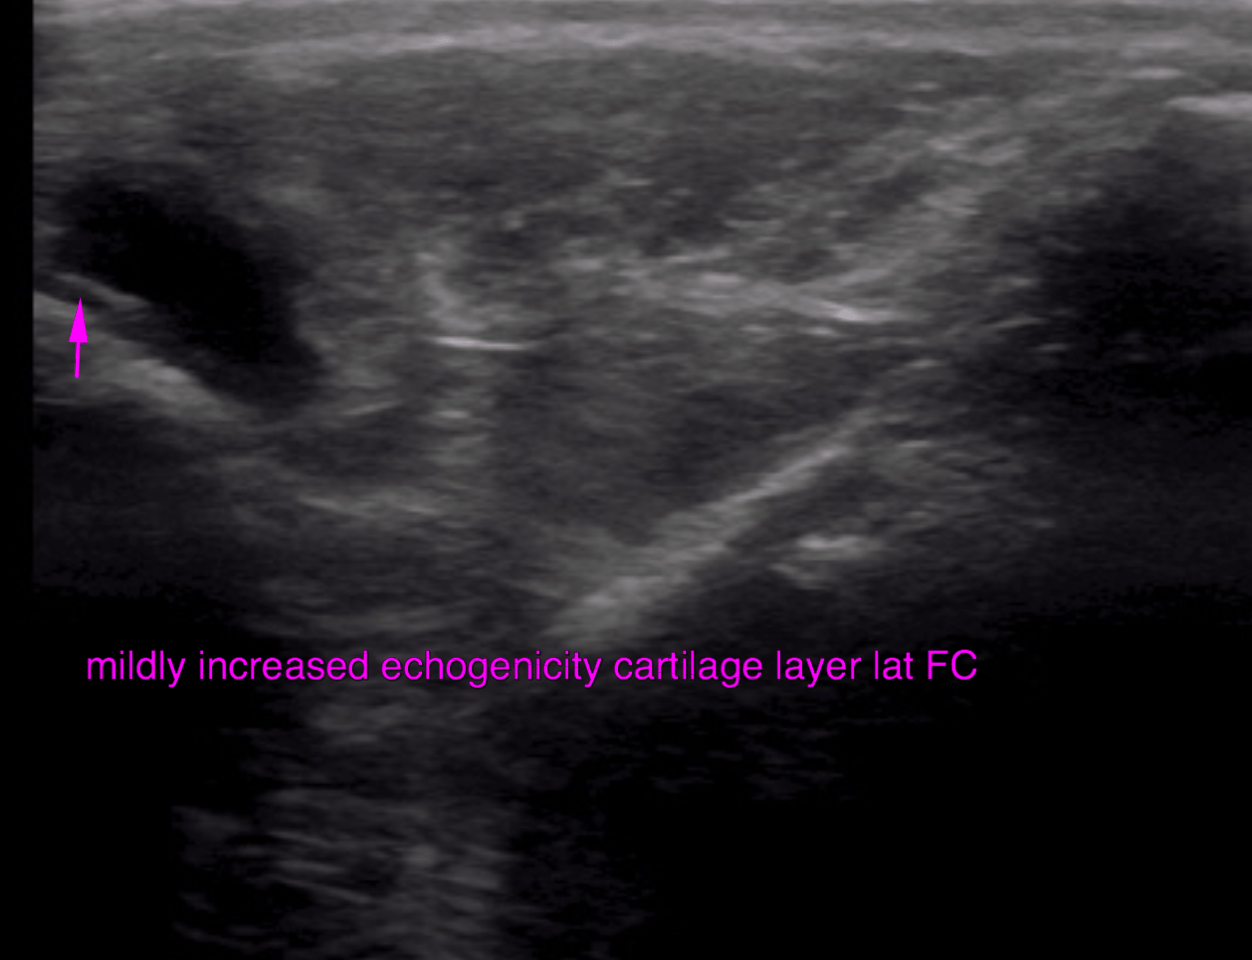

This 6 year old MN Belgian Shepherd dog has a history of intermittent lameness of over 1 year duration. Worsens with exercise. Decreased muscle mass right hind. Positive cranial drawer sign and CTT, moderate medial buttress sign.

Evaluate right stifle prior to TTA stabilization